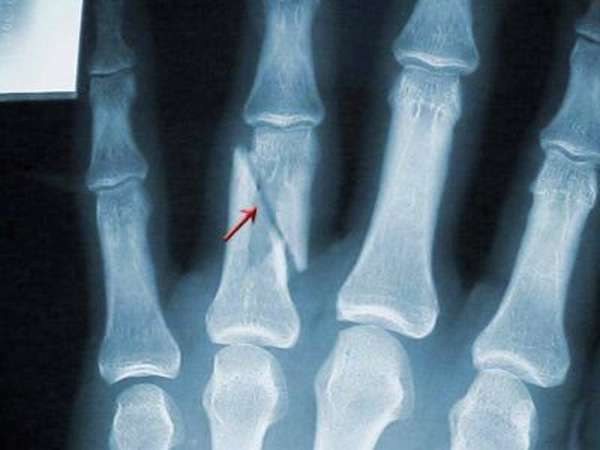

Механизмы повреждений пальцев кисти

Чаще травмируются основные фаланги 1, 3 пальцев. Для 3-го пальца типичными считаются переломы средних фаланг. Ногтевые повреждения характерны для 1-го и 5-го пальца. Формируются косые, косопоперечные и винтообразные переломы. Наблюдаются многооскольчатые переломы с наползанием отломков друг на друга. Этому способствует особое анатомическое строение кисти с высокой степенью подвижности ее образований.

Механизм травмы при переломе ногтевых, средних и основных фаланг прямой. Причина – сдавление, размозжение, ушиб.

При ударе по выпрямленному пальцу происходит резкое и чрезмерное сгибание его кончика. Палец с загнутым кончиком становится похожим на молоток. Отсюда и название повреждения «молоткообразный палец». Он остается в таком положении и может выпрямиться только с помощью другой руки. Это результат травмы сухожилия разгибающей мышцы. Большинство таких травм при должном лечении заживает без проблем.

Переломы делят на две группы в зависимости от того, как расположены отломки: со смещением, без смещения. Перелом пальца со смещением может быть с расхождением или захождением отломков.

По количеству осколков выделяют: безоскольчатые, одно-, двух- и многооскольчатые. По форме линии разлома различают поперечный, винтовой, косой, Т-образный, S-образный и другие виды повреждения. По месторасположению бывают околосуставные, внутрисуставные и внесуставные или переломы диафизарной части.